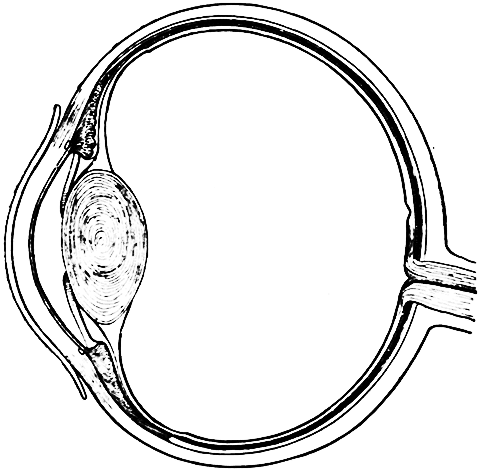

| 31. | The Human Eye | 274 |

| 32. | Retina of the Eye | 274 |